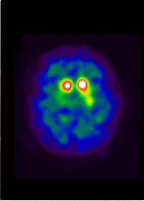

■ドパミントランスポーターシンチグラフィー(Dat Scan®)

正常な場合は、ドパミントランスポーターに集積された薬剤が三日月形、あるいはカンマ形を示す。

パーキンソン病の場合は、薬剤の集積量が低下したり、左右が非対称の形になったりする。

正常

パーキンソン病